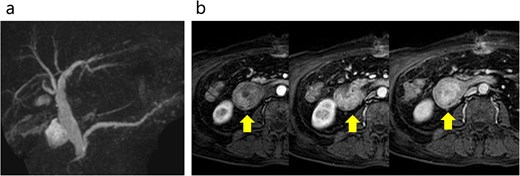

A 70-year-old male who worked as a farmer following retirement from office-work was referred to our hospital with anorexia, nausea, and abdominal pain. The patient had a history of hypertension, diabetes mellitus, gastroesophageal reflux disease, and benign prostatic hyperplasia. He had not smoked for 10 years and consumed one glass of the alcoholic beverage shochu daily. Contrast-enhanced computed tomography (CT) of the abdomen revealed peritonitis/duodenal perforation and a 4 cm duodenal tumor in the 1st and 2nd duodenum portions, respectively (Fig. 1a–c). Emergency laparotomy was performed to close the perforation. Gastroduodenal endoscopy revealed duodenal stenosis with a tumor in the 2nd portion (Fig. 2). Biopsy indicated a poorly differentiated adenocarcinoma; however, magnetic resonance imaging (MRI) showed no stenosis in the bile or pancreatic ducts (Fig. 3a and b). Preoperative laboratory data revealed normal levels of the tumor markers carcinoembryonic antigen (CEA) 1.5 (<5.0) and CA19–9 12.6 (<37.0).

Abdominal MRI. (a) No stenosis was observed in the bile or pancreatic ducts. (b) Contrast enhanced MRI revealed early dark staining in the duodenal tumor. The arrows indicate the tumor.